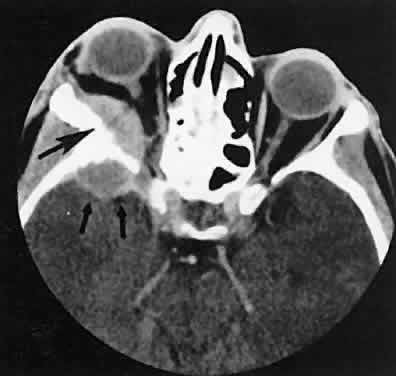

| The edema and inflammatory infiltrate that accompany infections are indistinguishable

from that associated with orbital inflammations. The presence

of sinus disease, however, is a more constant feature with infections, because

the sinus represents the infectious nidus in most cases (Fig. 9). In addition to the frequent appearance of sinus disease, the adjacent

EOM is invariably enlarged. Less often, orbital infections may be transmitted

through the blood, related to a retained foreign body, or spread

from the lids. Chandler and colleagues47 classified orbital infections into five groups. Group 1 (preseptal cellulitis) represents

inflammatory edema and reflects congestion of venous

outflow. Group 2 has actual orbital infiltration/edema with mass effects

and functional deficits. Group 3 includes patients with subperiosteal

abscesses. Most of these dome-shaped subperiosteal abscesses are

located along the medial wall. Group 4 includes patients with orbital

abscesses who may display a ring-enhancing lesion with mass effect. Group 5 represents

intracranial extension of the inflammation into the

cavernous sinus or sinuses, which appear engorged and opacified. Harris48 related the clinical course of patients with subperiosteal abscesses to their CT scans. The sub-periosteal material could not be predicted from the size or the relative radiodensity of the collections on the scan. Serial scans also showed enlargement of the abscess during the first few days of intravenous antibiotic therapy, regardless of the ultimate response to therapy. |